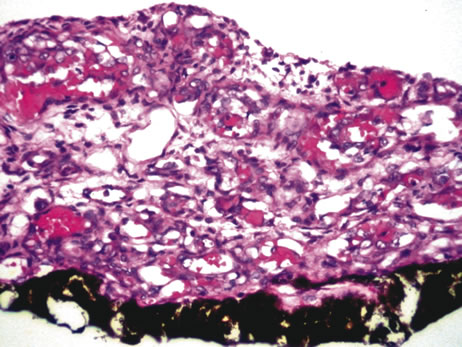

Infectious endophthalmitis refers to inflammation due to an infectious organism, usually bacterial, but it may also be caused by yeast or filamentous fungi. The vitreous is typically involved and supports the growth of the infectious intraocular organism. The reaction to the organism is usually severe and is characterized by abundant polymorphonuclear leukocyte infiltration. The infection is usually accompanied by tissue destruction due to the release of proteolytic enzymes in the severe inflammatory reaction. Uveal and retinal necrosis may occur during these infections. Endogenous endophthalmitis refers to hematogenous dissemination of organisms to the eye and can be seen in cases of septicemia from bacterial or fungal causes. The latter can be caused by Candida or Aspergillus species. Aspergillosis usually causes destructive choroidal inflammation (Fig. 24) with vascular occlusions. The infective organisms are found in the choriocapillaris or along the sub-RPE and sub-retinal space.126

Fig. 24. Aspergillus chorioretinitis. A. Hemorrhagic necrotizing retinitis and choroiditis are noted in a patient with disseminated aspergillosis (hemotoxylin-eosin ×60). B. Note the branching hypae of the organisms involving the retina and choroid (periodic acid–Schiff ×240).